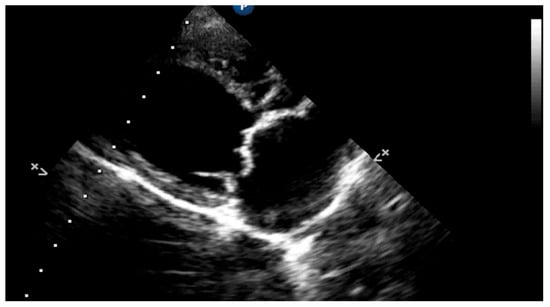

5.1.1. Measurement of Left Ventricular Volume by Simpson’s Method of Disks and Left Ventricular M-Mode